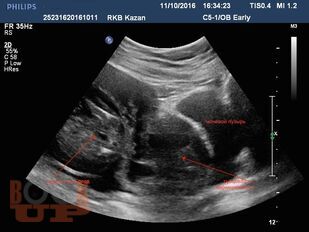

В методических рекомендациях приведен сравнительный анализ существующих методов лечения беременности в рубце на матке после кесарева сечения в нижнем сегменте. Подробно изложен собственный запатентованный протокол лечения рубцовой беременности в зависимости от данных ультразвукового исследования в совокупности с уровнем ХГЧ в сыворотке крови беременной, разработанный авторами. Данный протокол позволяет на основании полученных диагностических данных выбрать оптимальный метод органосохраняющего лечения, определить методы последующего контроля состояния пациента.